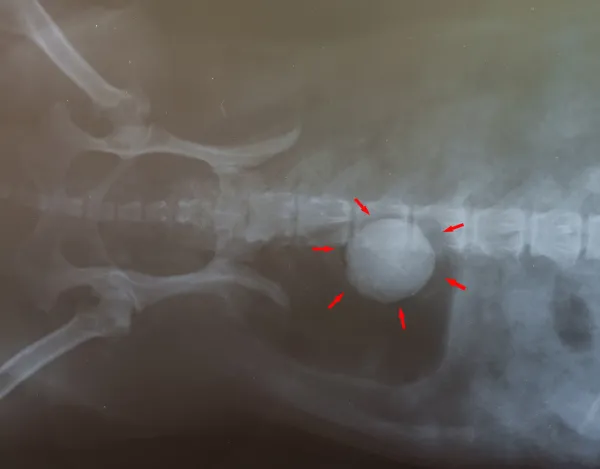

Ingestión de un cuerpo extraño - Hospital Veterinari de Catalunya